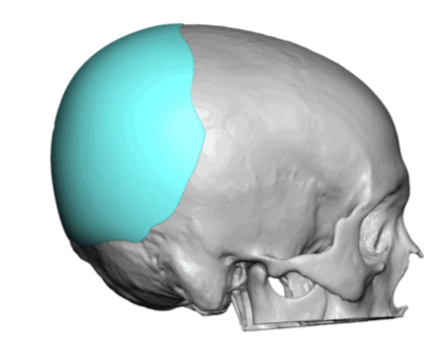

Desire for a higher and more prominent crown of the skull.

Crown of skull augmentation using a custom skull implant.

Desire for a higher and more prominent crown of the skull.

Crown of skull augmentation using a custom skull implant.